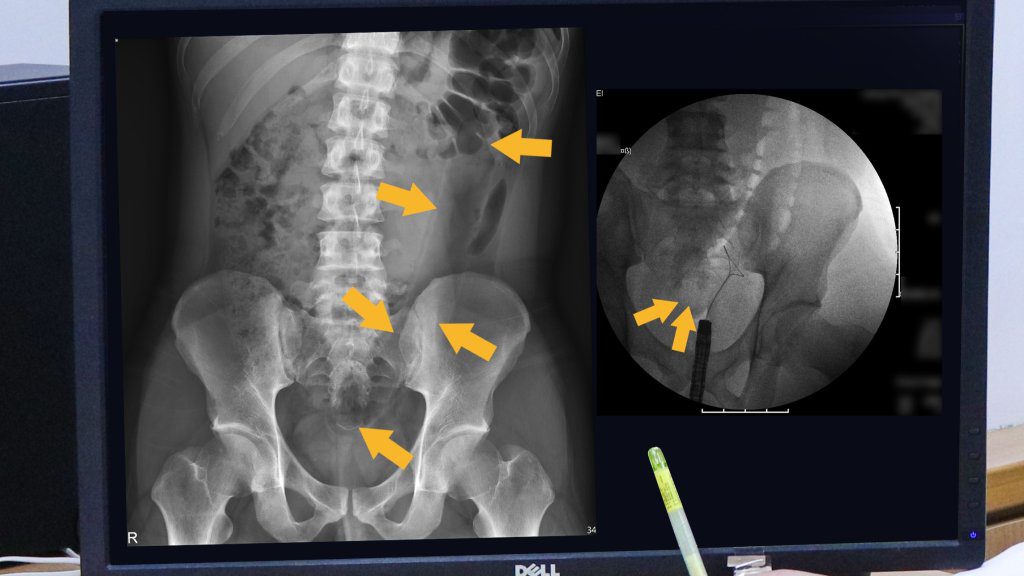

羅東博愛醫院外科部部主任李明璋醫師指出,該男子將長條形按摩棒完全插入直腸,本以為能自行排出,但一夜過去未能如願,隔日清晨開始出現下腹劇烈疼痛,只好緊急前往急診求醫。急診醫師進行直腸觸診時並未觸及異物,隨後進一步安排X光檢查,才確認該按摩棒已深嵌於乙狀結腸內,底部距離肛門口約20公分,頂端甚至深入降結腸。

幸好這名男子的大腸尚未出現破裂情形,李明璋隨即與肝膽腸胃科陳明杰、何欣玲醫師組成跨科醫療團隊,在X光透視即時影像輔助下,以大腸鏡搭配特製取物工具,成功將長約35公分的矽膠按摩棒從肛門完整夾出,讓患者免於開腹手術之苦。李明璋強調,這是全台首例無需開刀、透過內視鏡從肛門成功移除深藏乙狀結腸巨大異物的案例,創新技術可望幫助更多患者,他也提醒,民眾使用情趣用品時務必遵守安全原則,選擇具防脫落設計的器具並注意使用分寸,以免造成難以挽回的傷害。